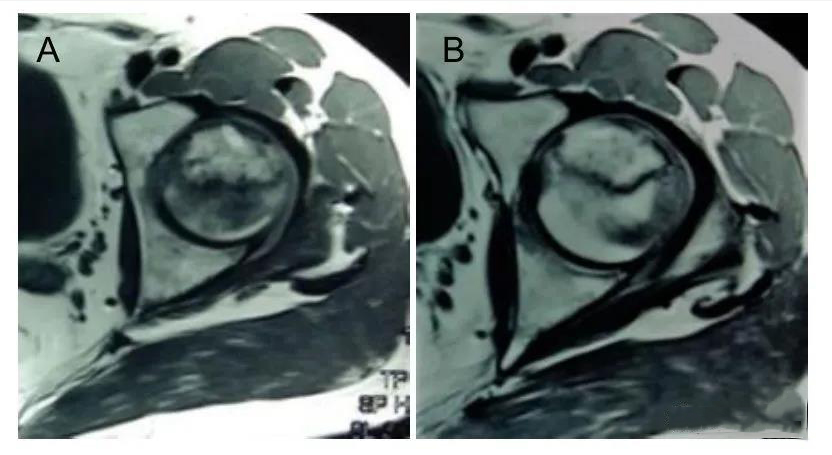

此外,MRI片上坏死面积较术前明显减小,细胞使用前坏死面积为(31.0±5.3)mm2,细胞使用后为(24.3±3.5)mm2,具有差别意义。

图A:MRI图像股骨头坏死;

图B:显示细胞使用后股骨头坏死面积缩小。